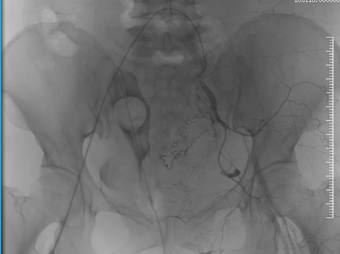

患者因外伤来诊时,CT检查提示骨盆骨折伴盆腔血肿,同时意外发现Stanford B型主动脉夹层——这是两个都可能危及生命的急症。面对如此复杂情况,介入科团队第一时间行动。

在患者生命体征尚平稳但潜在风险极高的情况下,我们结合CT增强检查及三维重建结果,考虑盆腔存在活动性出血,果断通过绿色通道经股动脉穿刺行盆腔动脉造影,竟发现至少3条动脉存在损伤情况。随即迅速以导丝导管结合技术超选择插管至出血责任动脉并成功实施栓塞术。相对传统开腹探查手术,这项微创介入技术不仅大大节省了宝贵的抢救时间,更是避免了开腹手术的创伤,用最小的代价稳定了患者的生命体征,为后续治疗赢得了宝贵时间。